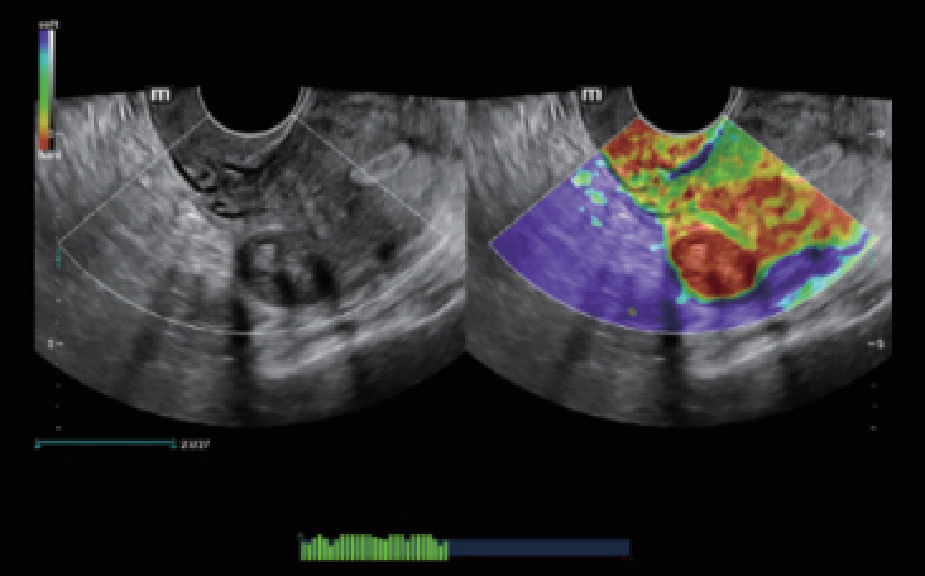

Platforma ZST+ to zaawansowane technologiczne narz?dzie, kt├│re zast?puje tradycyjne formowanie wi?zki, przetwarzaniem opartym na danych kana?owych. Dzi?ki temu przezwyci??a ograniczenia zwi?zane z kompromisem pomi?dzy rozdzielczo?ci? przestrzenn?, rozdzielczo?ci? czasow? i jednorodno?ci? tkanki, kt├│re wyst?puj? w tradycyjnych ultrasonografach.

Obrazy kliniczne